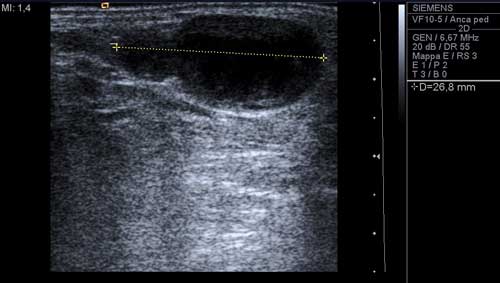

L�esame

ultrasonografico, condotto con sonda lineare da 10 MhZ, dimostrava,

nel sottocute del 1� spazio intermetatarsale del piede dx, la

presenza di una formazione rotondeggiante, con aspetto a clessidra

asimmetrica, rinforzo di parete posteriore, ben delimitata,

dimensioni 18 x 11 x 26 mm, con centro anecogeno e periferia

debolmente ecogena con parete esterna nettamente delimitata e vallo

interno irregolarmente sfrangiato (Figura 1), localizzata

immediatamente a valle della biforcazione della arteria pedidia nel

ramo plantare profondo e nella 1a metatarsale dorsale,

arteria che appariva decorrere, sia pure in maniera irregolare, lungo

la parete mediale della formazione (Figura 2)

Figura 1. Ecografia-scansione longitudinale con misurazione del diametro massimo. |